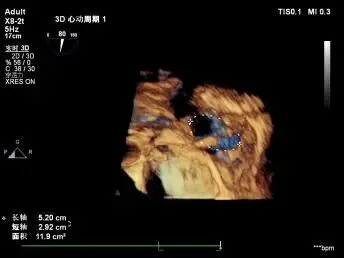

1. 瓣环面积由18.7降至11.9,瓣环面积减少36%。

2. 术前反流4+降至1+。

3. 临床恢复情况:术后无出血、心包填塞、严重心律失常等并发症;出院前患者NYHA心功能分级由IV级提升至II级,超声复查TR维持1+,无器械相关不良事件,随访结果进一步验证了手术的有效性与安全性。